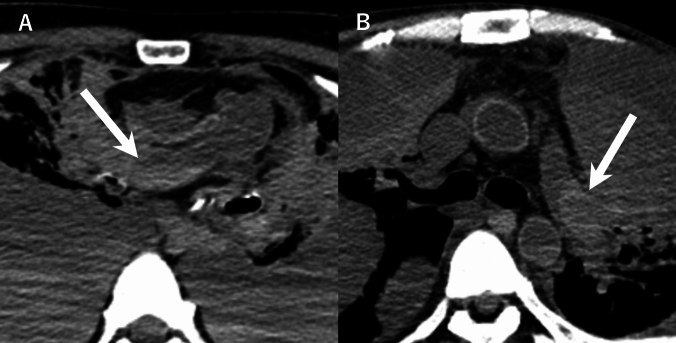

目的:尸体计算机断层扫描(PMCT)通常显示心脏和血管结构中的血凝块和沉淀。我们检查了这些死后发现与院内死亡的死前临床和实验室参数之间的关系。材料和方法:这项前瞻性研究包括114例死后24小时内进行PMCT的非创伤性院内死亡。两名放射科医生评估了左右心房、肺动脉和胸主动脉的高密度区域,并将其分类为血凝块或重力沉降。采用单因素和多因素logistic回归分析死亡前一周的临床和实验室数据。结果:所有解剖部位的观察者间一致性极好(κ = 0.87-0.91)。34-53%的病例在不同部位观察到血凝块或血液沉淀。根据单因素分析,非肺炎感染、阳性血培养和升高的凝血参数(凝血酶原时间-国际标准化比率、活化的部分凝血活酶时间)与重力沉降有关。相反,实体恶性肿瘤和较高的血液学参数(血小板计数、红细胞、血红蛋白、中性粒细胞百分比)与血块形成相关(均p)。结论:死后重力沉降与非肺炎感染有关,而血块形成与较高的血小板计数有关。这些发现为解释PMCT的发现提供了客观标准,并可能有助于评估患者生前的临床状态,特别是在临床信息有限的情况下。

Material and methods: This prospective study included 114 non-traumatic in-hospital deaths where PMCT was performed within 24 h postmortem. Two radiologists evaluated high-density areas in the right and left atria, pulmonary artery, and thoracic aorta, and classified them as blood clots or gravitational sedimentation. The clinical and laboratory data from the week before death were analyzed using univariate and multivariate logistic regression.

Results: Interobserver agreement was excellent for all anatomical sites (κ = 0.87-0.91). Blood clot or blood sedimentation were observed in 34-53% of cases across different locations. Per univariate analysis, non-pneumonic infections, positive blood cultures, and elevated coagulation parameters (prothrombin time-international normalized ratio, activated partial thromboplastin time) were associated with gravitational sedimentation. In contrast, solid malignancies and higher values of hematologic parameters (platelet count, red blood cells, hemoglobin, neutrophil percentage) were associated with blood clot formation (all p < .05). Per multivariate analysis, non-pneumonic infections maintained strong associations with gravitational sedimentation across all sites (p < .05), while higher platelet counts independently predicted blood clot formation in the right atrium, left atrium, and thoracic aorta (p < .05).